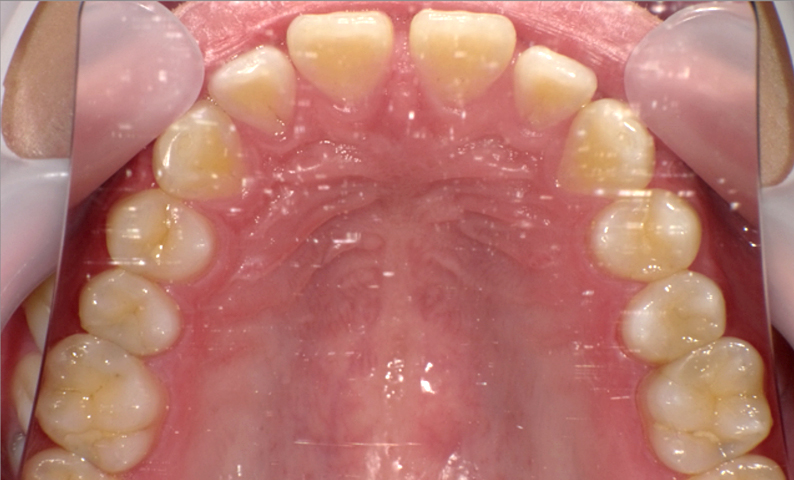

| 治療前 | 治療後 |

|---|---|

|